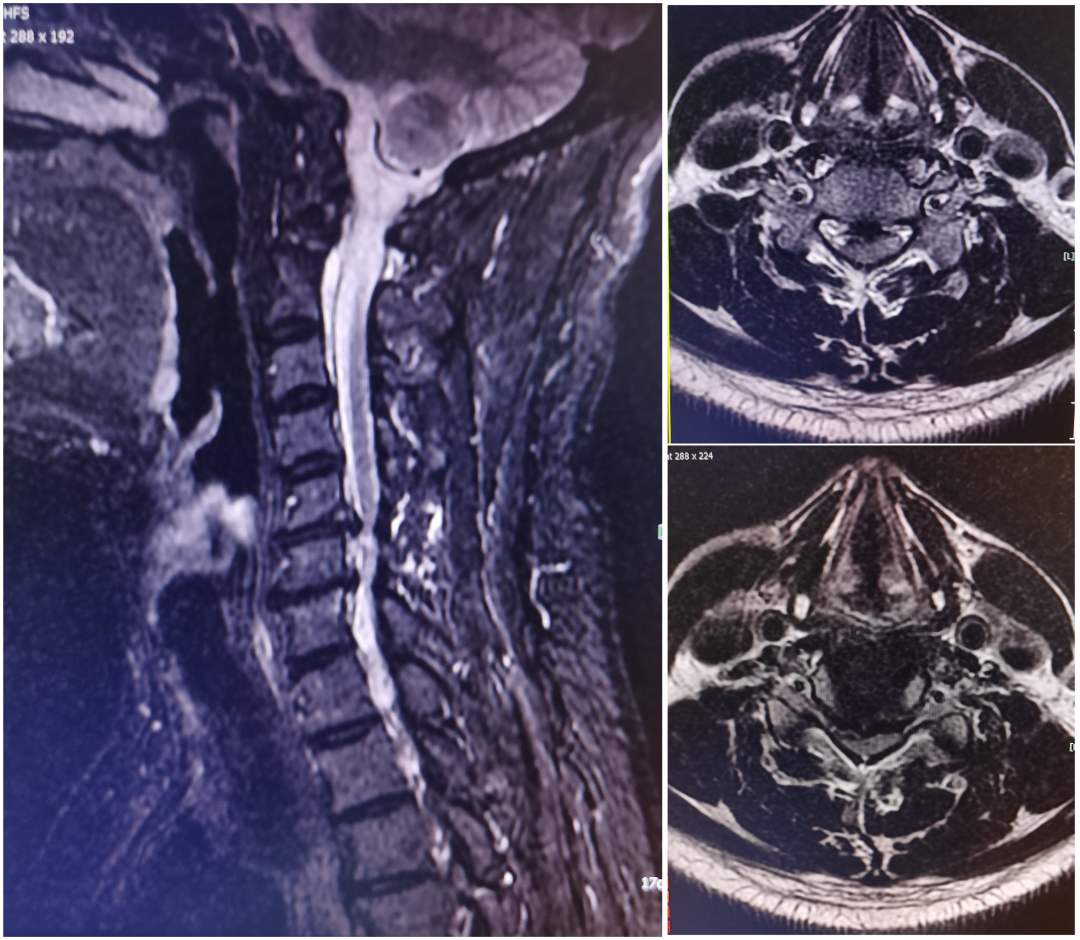

颈椎前路微创(ACDF)

患者,叶某,中老年男性,因四肢麻痛、乏力1年余入住我院脊柱外科,查体:颈项部肌肉稍紧张,颈部活动受限,双手及双下肢感觉减退,双手握力约3级,双侧耸肩、肱二头肌、肱三头肌4级,双下肢肌力约4级,四肢肌张力稍高,双侧Hoffman征(+)。结合患者病史及影像学检查,诊断:脊髓型颈椎病,于全麻行微创经颈前路颈5/6、颈6/7椎间盘摘除、椎间融合器融合、钢板螺钉内固定术。患者术后四肢麻痛症状明显改善,术后第3天佩戴支具下床活动。

术前影像学

术后复查、术后切口